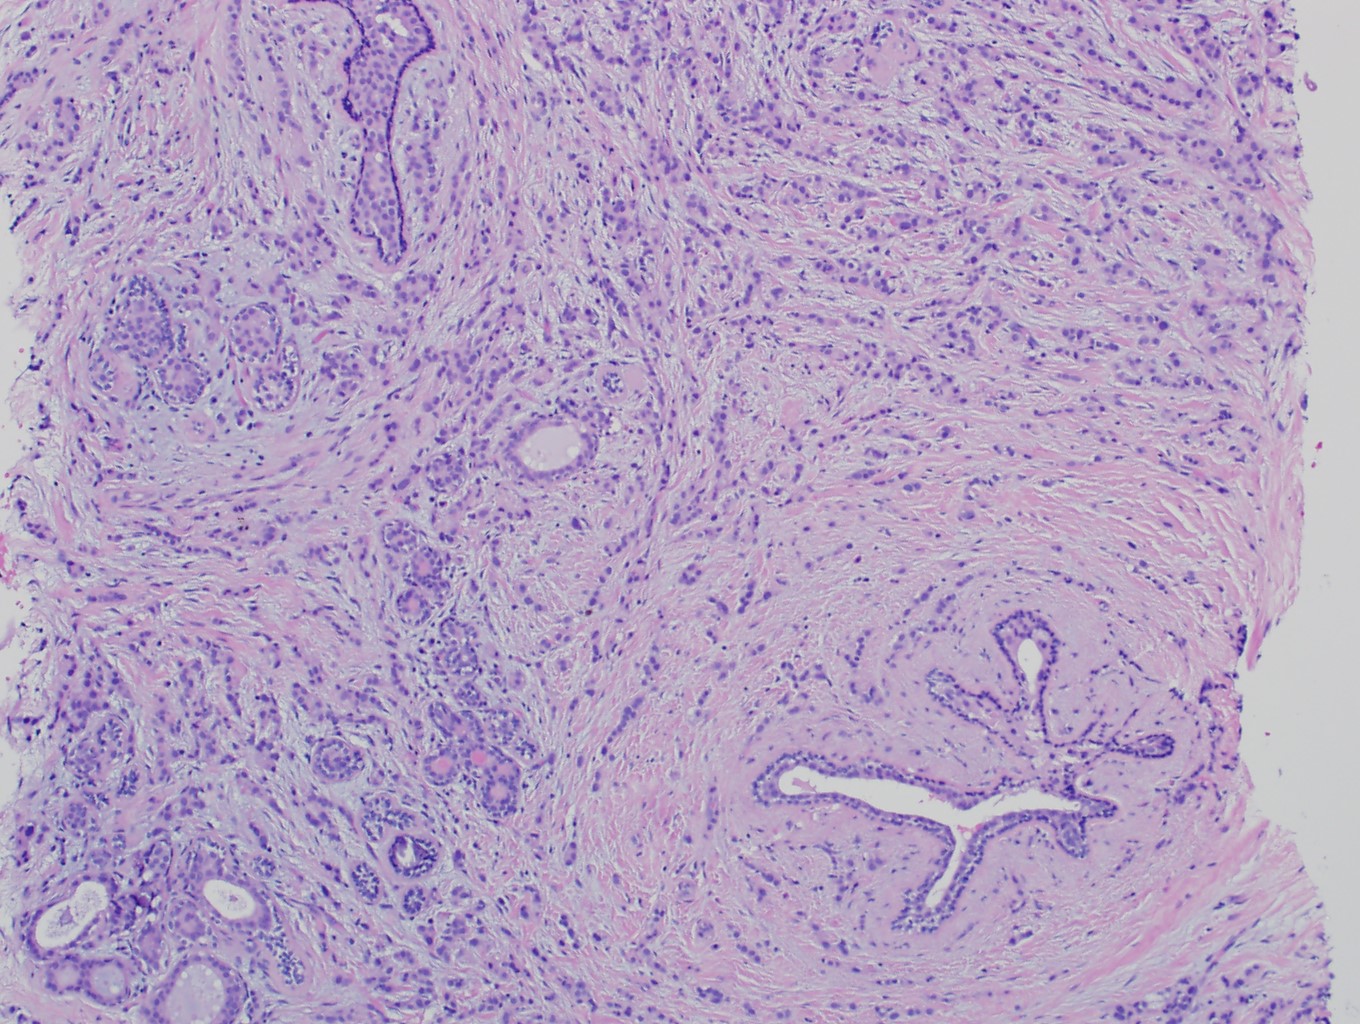

Microscopic (histologic) description

- Histological features of IBC NST vary considerably from case to case and even within the same case

- Margins vary from highly infiltrative, permeating the surrounding tissue, to continuous pushing margins

- Architecture varies from sheets, nests, clusters, cords or individual cells (but lacks the cytomorphological characteristics of invasive lobular carcinoma)

- Tubular formations are prominent in well differentiated tumors but absent in poorly differentiated tumors

- 2 distinct growth patterns exist:

- Tumors characterized by small cancer nests accompanied by marked fibrosis (desmoplastic / scirrhous); this type diffusely infiltrates the surrounding tissue as an irregular shaped spiculated mass

- Often ductal carcinoma in situ (DCIS) (up to 80%)

- In some cases, DCIS is extensive

- Associated DCIS is usually of same nuclear grade as the invasive carcinoma

- No myoepithelial cell lining (as seen in DCIS or benign lesions)

Microscopic (histologic) images

Contributed by Julie M. Jorns, M.D., Kristen E. Muller, D.O., Gary Tozbikian, M.D. and Emad Rakha, M.D.